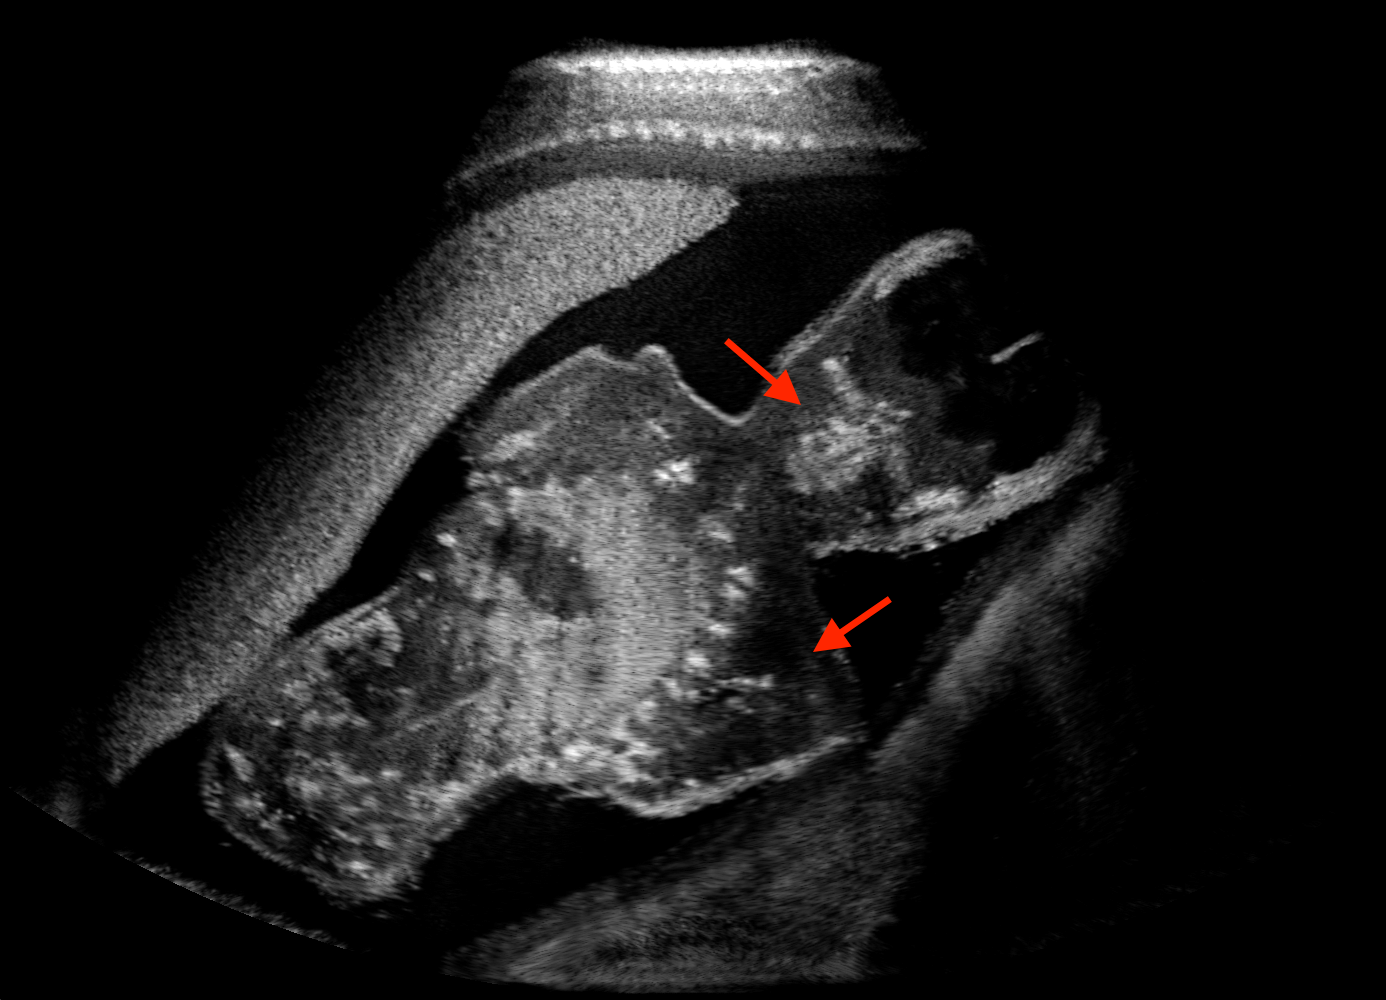

For the interpretation of the local errors, sample spatial p error maps are depicted in Fig. 3 for LSA2H, NSA2H, and SA2H for the middle two examples shown in Fig. 2. Both images generated by NSA2H have a lot of missing structures and accordingly have high error almost all over the map. Artificial skull enhancement with LSA2H is seem to evoke large p error, as shown in the corresponding error map, whereas the bright spots in the error map of SA2H reflect some hallucinated shadows and structure in the brain. All of above mentioned regions of interest are marked by red arrows. In the bottom example, SA2H fails to generate faithful content at the bottom region marked by red circles, which is well indicated by the error map as well.